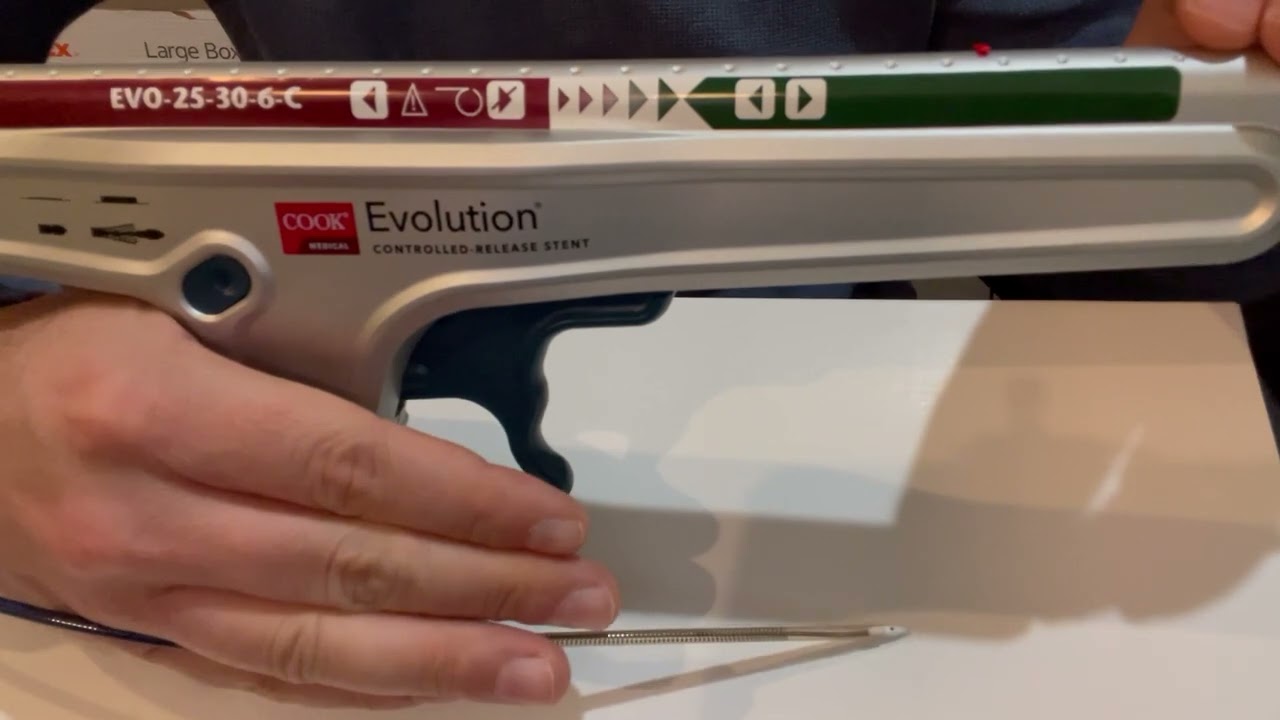

According to a study in Frontiers in Cardiovascular Medicine, alternative balloon-based approaches are effective ...